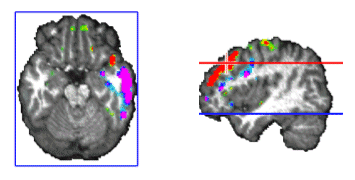

One interesting finding of this analysis was that we often observe strong activity localized at brain voxels located at near the putative position of the thalamus in our head model. Such deep activity corresponded even with the maximum or the minimum at some punctual times that preceded the spindles. Such strong thalamic activity was never observed at the spindle during the times of maximal spindle waning or waxing. Later observation reveals that deep brain activity can be observed at the scalp and thus localized with inverse solutions when the cortical areas are relatively silent and the deep activity is strong. This is likely to be the case for sleep spindles for which thalamus is known to be a basic generator. One example of such activation is presented in Figure 9.

Figure 9. Voxels at the putative localization of the thalamus can appear as the maxima or the minima of the activity recovered by ELECTRA inverse solution. Here the maximum is indicated by the red cross. Thalamic activity was often observed preceding the start of the spindle, i.e. when cortical areas were practically silent.

We were also interested in analyzing the stability and generators of the activity during the inter-spindles intervals. Experimental evidence (Sirota, et al. 2003) indicates that sleep spindles promote hipoccampas ripples after a certain temporal delay. It is therefore interesting to explore the areas activated after spindles. We did in fact found stable activity after all spindles explored. The stability occurred preferentially after the slower 12 Hz spindles that showed maxima at temporal brain areas. In general the frontal maximum observed during the spindle shifted toward temporal areas of the same hemisphere where the frontal maximum was found. This effect is illustrated in Figure 10. The sequence of maps show the end of the spindle with the right frontal maximum and minimum followed by the increase in activation at the right middle temporal lobe that soon becomes the maximum. Activity is progressively shifted towards the right superior temporal gyrus. The axial slide shown in Figure 11, at the level of the blue line shown in the rightmost inset, illustrates that the temporal activity observed after spindles is not restricted to the cortex but also involves deep temporal lobe structures such as the hippocampal/amygdala formation.

Figure 11. Simultaneous cortical and subcortical activity (amygdala/hippocampus formation) is observed during the interspindles interval.